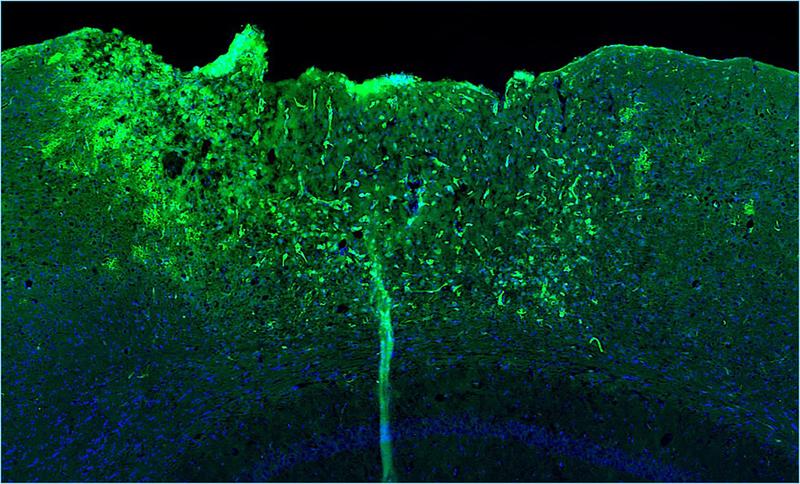

Die fluoreszenzmikroskopische Aufnahme zeigt in unmittelbarer Nähe der Verletzung eine hohe Aktivität des Genregulators NF-kB (grüne Signale).

Die fluoreszenzmikroskopische Aufnahme zeigt in unmittelbarer Nähe der Verletzung eine hohe Aktivität des Genregulators NF-kB (grüne Signale). Außerhalb des Wundgebiets sind die Gehirnzellen ohne NF-kB Aktivität und erscheinen deshalb in Blau Copyright: Abb: doi.org/10.1038/s41467-026-70304-7